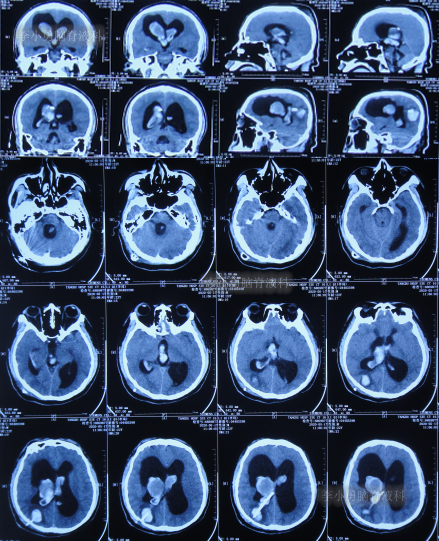

发现脑积水15年后即2020年1月份,开始出现头胀头闷能自行缓解,并没有特殊处理,3月后即2020年4月8日,因症状变重且变频繁,至甘肃省天水市某医院检查头颅核磁(图-3)认为脑积水较前(2016年7月20日头颅CT)加重。

图-3:2020年4月8日头颅核磁